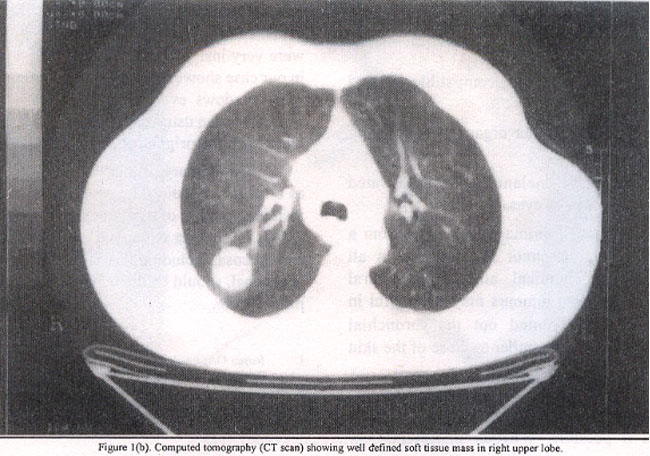

A 74 years old man was referred by a chest physician for resection of an incidentally discovered solitary tumor in right lung. The patient initially presented with non-specific back pain in October 2000. Subsequent chest X-ray well-circumscribed mass, 40 mm in maximal diameter, that was 32mm from the bronchial margin was noticed. It approached close to, but did not involve the pleural surface.